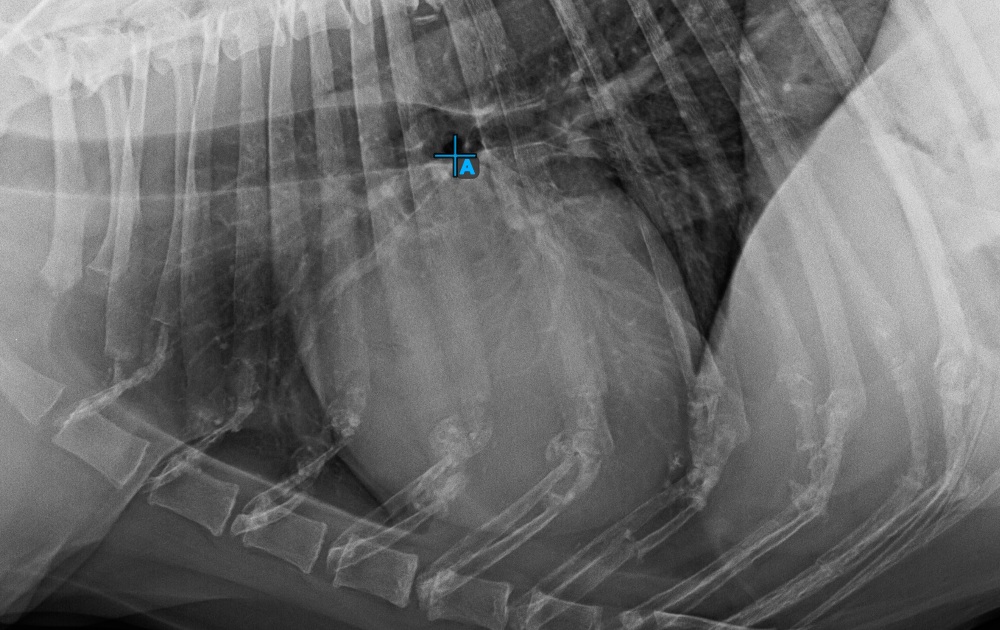

Fejezze be a szív hosszanti tengelyét az Apex pont megjelölésével, a szív alsó részéhez közel.

Az alábbi kép az Apex pont tipikus elhelyezkedését mutatja.